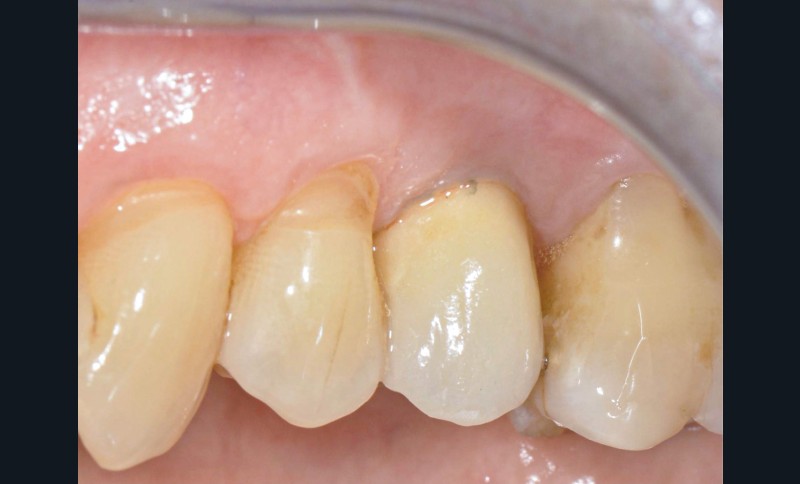

La patiente

- 61 ans

- Sous bêta-bloquant

- Bonne hygiène orale

- Parodontite traitée et stabilisée depuis 2016

- Maintenances tous les 6 mois

L’implant

- Posé en 2019 par son dentiste

- Couronne d’usage transvissée

- Péri-implantite diagnostiquée en 2020